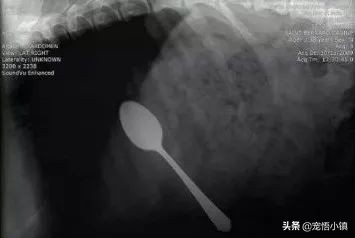

如果玩具较小,一直没有找到的话,那么很有可能在狗狗的肚子中!怀疑的话,带着狗狗拍片,随后就会发现:

(勺子?!!!)

日常用品类:橡皮、塑胶袋、瓶盖、针线、牙刷、肥皂、吸铁石、充电器头、耳机、勺子等等。玩具类:小型塑料玩具、绳结玩具、积木、拼图、易拆卸玩具等等。食物类:各种骨头。异物类:石头、树枝、果核等等。